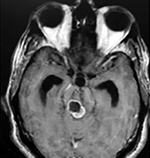

EJEMPLO DE CASO CLÍNICO (8)

Paciente femenino de 29 años de edad con historial de cefalea crónica que presenta súbitamente disdiadococinesia y dismetría izquierda.

El estudio de RMN presenta una lesión bien circunscrita en hemisferio cerebeloso izquierdo con periferia de predominio hiperintenso en T1 y T2, y centro hipointenso, edema perilesional mínimo, así como una imagen de un vaso venoso alimentador que recorre hacia el ángulo pontocerebeloso izquierdo.

El estudio de control de RMN se observa la brecha quirúrgica y ausencia de lesión (figs. 1, 2 y 3).

Figura 1:

Lesión cerebelosa izquierda ponderaciones en T1 y T2, la flecha señala vaso nutricio hacia el ángulo pontocerebeloso izquierdo, se puede observar el centro de intensidad heterogénea con contenido quístico multiloculado y edema perilesional leve.